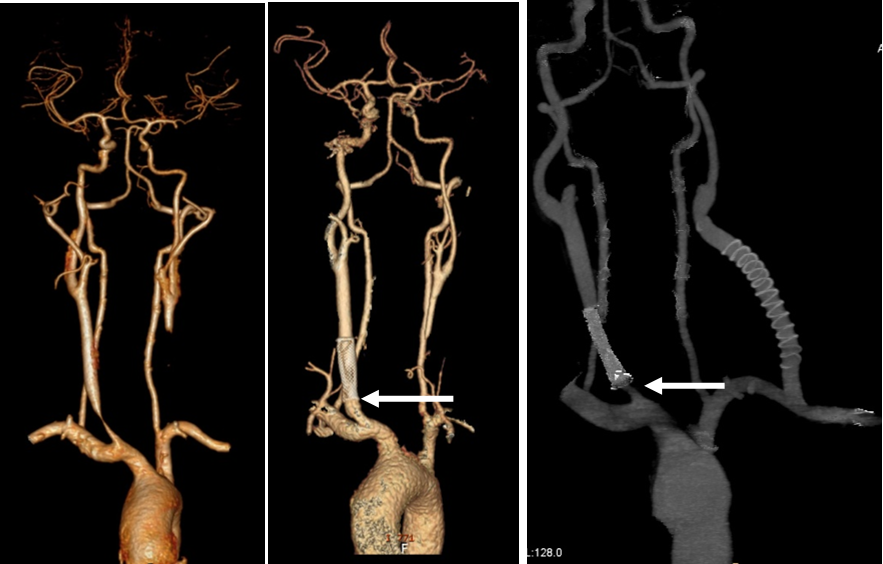

★ 病例3(女性,24岁)

症状:缺血性卒中;ESR 10mm/h, CRP 2.3mg/dl。

诊断:双侧颈总动脉闭塞。

启示:球扩覆膜支架重建颈总动脉近端血流,但复合手术需更多数据支持。

前循环缺血症状